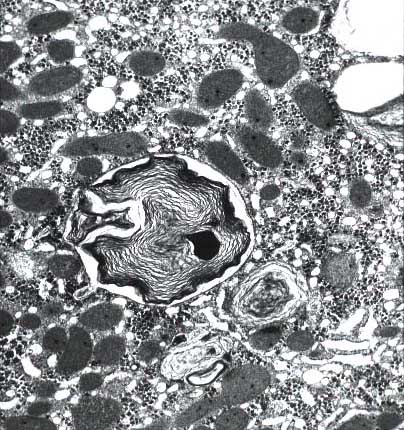

Phospholipidosis: there are foamy hepatocytes plus, under electron microscopy, large lysosomal inclusions composed of densely packed concentric membranes with a fingerprinting pattern. There is also reduction of the crystae in the mithochondria and vesicles in the smooth ER. The lesion was recognized by Oda in Japan in 1969. Later, in 1975, it was recognized by Lullman et al in inborn errors of phospholipid metabolism. Drugs responsible: Colargil (Oda et al. 1969), Amiodarone (Pousell et al.1984).

li-8-4-16.jpg (75249 bytes)

Fig. 8-4-16:

Giant Mitochondria

li-8-4-17.jpg (66449 bytes)

Fig. 8-4-17:

Myelin figures